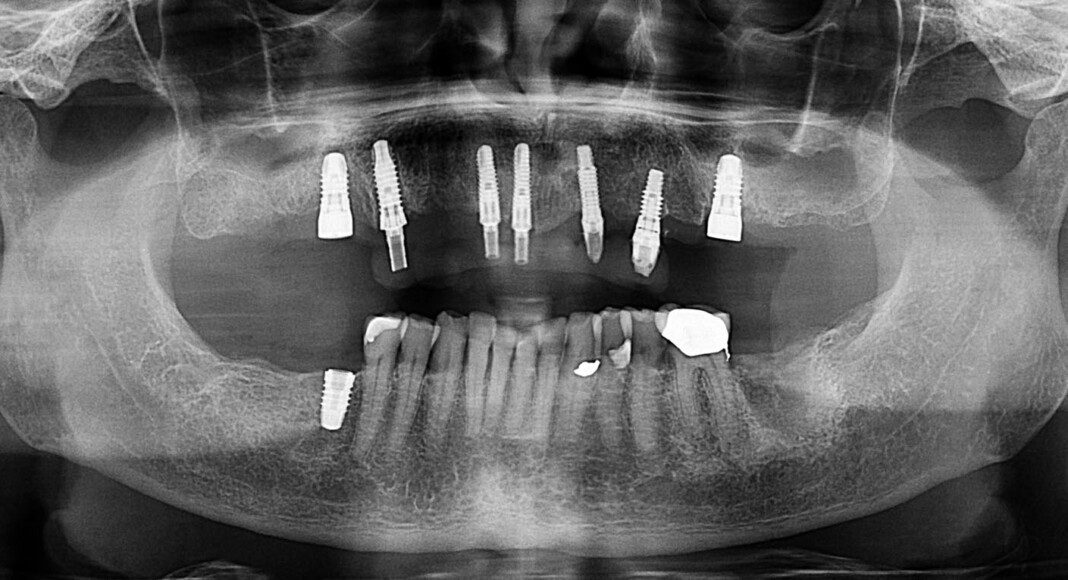

Pre-surgical view after removal of existing restorations. Existing implants were not perfect but reasonable. Better to use them than to try to remove and replace.